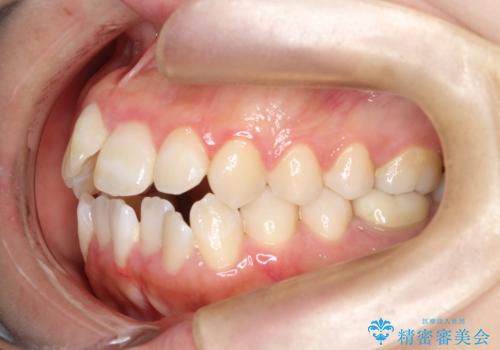

前歯のデコボコと開口を改善し、美しい口元へ

- 前歯のデコボコ(叢生)と、上下の歯が閉じない開口を主訴にご来院されました。精密な検査の結果、歯が並ぶスペースが不足しており、特に奥歯の咬み合わせが安定していないことが開口の原因と判明。患者様と相談し、上下左右の小臼歯を抜歯することでスペースを確保し、審美ワイヤー矯正で全体を整える治療計画を立案しました。これにより、見た目の改善だけでなく、機能的な咬み合わせも獲得することを目指します。

今回の矯正治療では、歯が並ぶスペースを確保するため、上下左右の小臼歯を抜歯しました。装置には目立ちにくい審美ワイヤーを使用し、見た目に配慮しながら治療を進めました。抜歯によってできたスペースを利用して歯を並べ、前歯のデコボコを解消。同時に、歯列全体を動かすことで、上下の歯がきちんと閉じる開口も改善しました。治療期間は約2年間。治療の結果、コンプレックスだった前歯のデコボコと開口が解消され、整った美しい歯並びと、しっかり咬める機能的な咬み合わせを獲得していただけました。